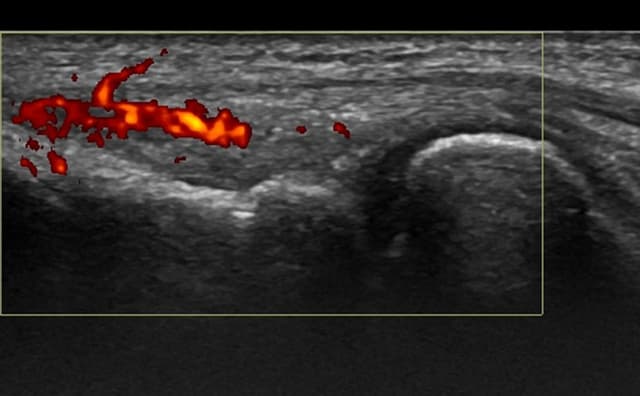

Enables clear visualization of anatomical landmarks, needle movements, and injection sites.

Hands-on Interventional Training – Introducing simulator-based hands-on interventional training. These are one-of-a-kind and replicate human anatomy, allowing users to perform injections under ultrasound guidance like performing real-world procedures.